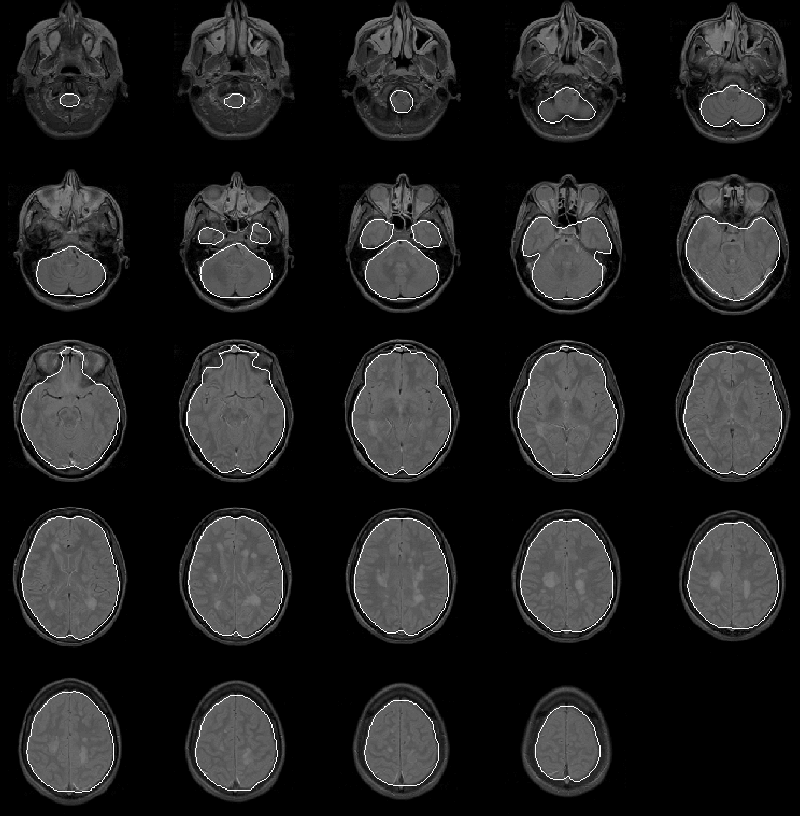

As illustrated by Figure 8.23, the Generate Final Brain Mask process produces results for Data Set 3 that are comparable to the results for the previous data sets. Slight errors occur in the lower slices, where the mask excludes low intensity brain tissues. Another small error occurs in slice 9 where the mask includes a tiny region for bright tissue outside the brain.

We have yet to acquire expert information regarding the intracranial boundary for Data Set 3. Expert validation of the final brain mask is again left for future work.

Figure 8.23: The final brain mask for MRI Data Set 3 overlaid on the PD-weighted scan.